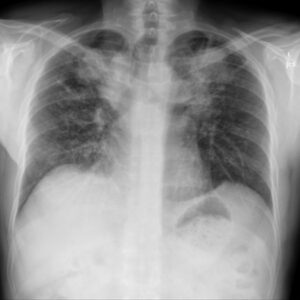

Two chest X-rays of a patient with silicosis taken one year apart, showing the progression of fibrosis.